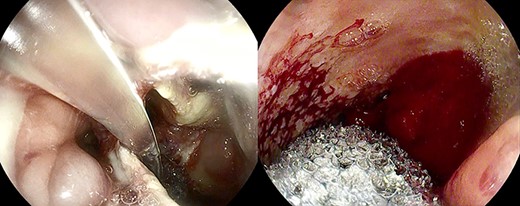

After the 14th session, the endoscopic evaluation showed a significantly cleaner and smaller cavity (1 cm). Two esophageal fully covered SEMS (Taewoong Niti-S Beta Stent) allowed the patient to have a liquid diet while the leak was safely healing: the stents were subsequently placed and kept for 3 weeks each. Endoscopy and esophagram were performed after SEMS removal, and they demonstrated leak resolution, with a tiny persistent depression at the site (Fig. 4). The patient has not had symptoms of recurrent fistula formation for over 6 months.